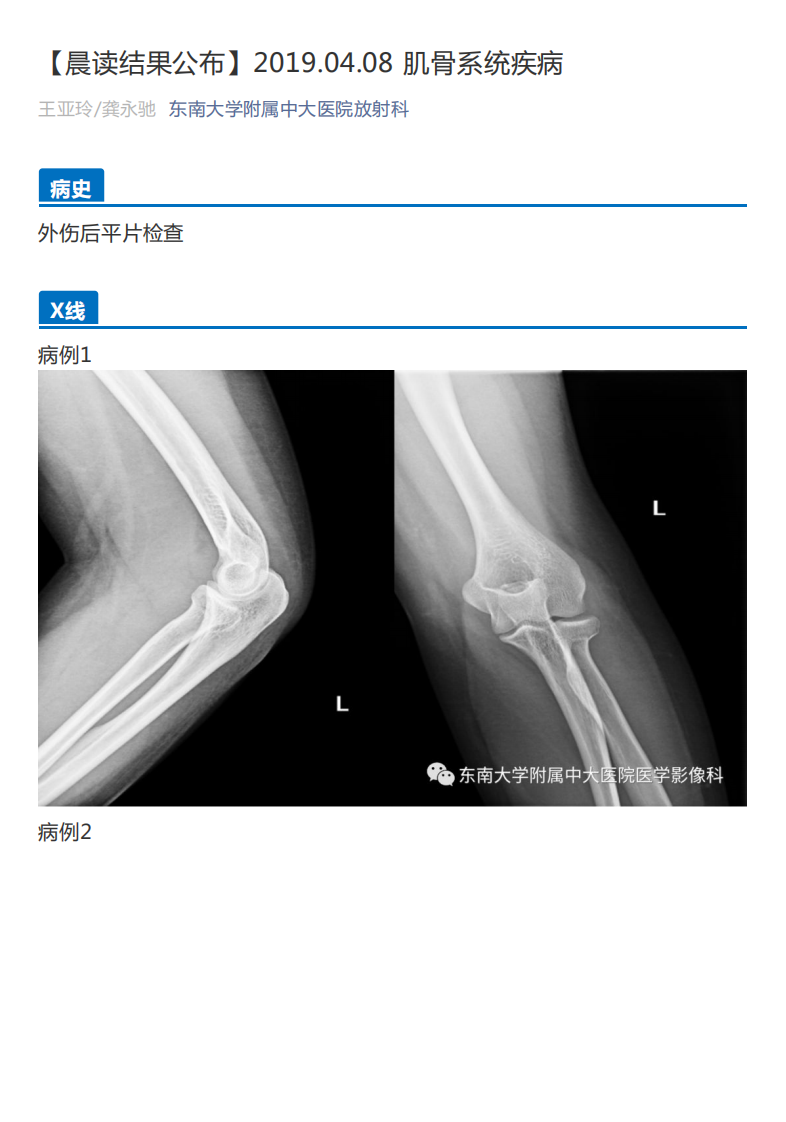

20190409_2【晨读结果公布】2019.04.08肌骨系统疾病.pdf

39页

温馨提示:当前文档最多只能预览 5 页,若文档总页数超出了 5 页,请下载原文档以浏览全部内容。

剩余34页未读,

下载浏览全部